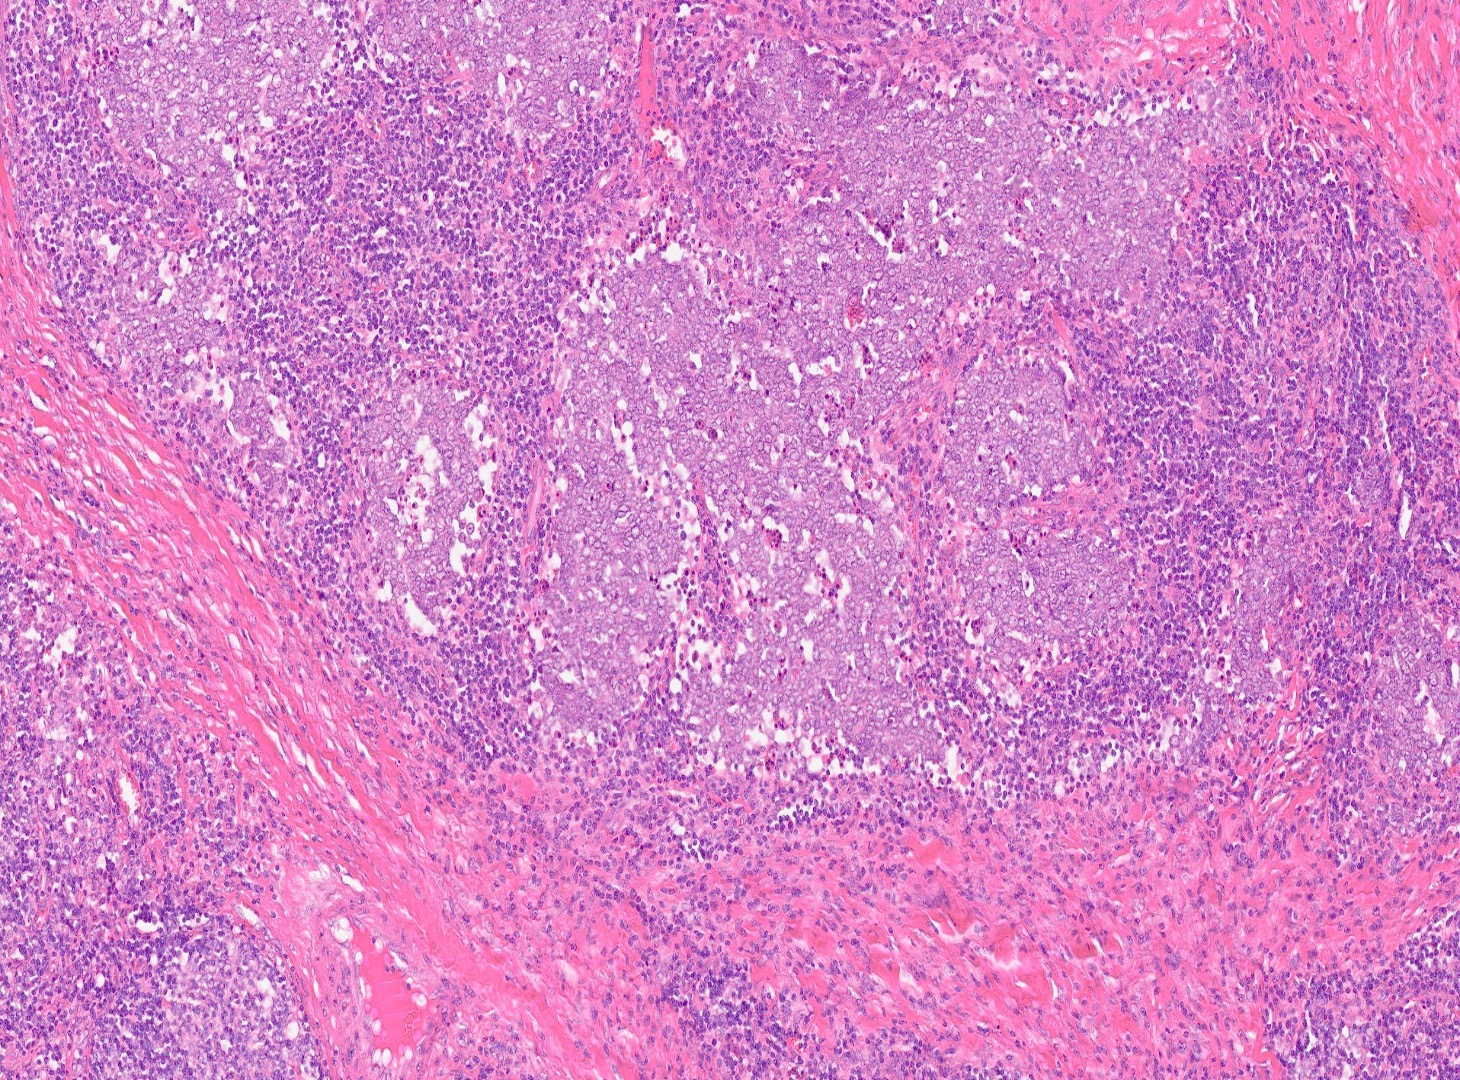

H&Ex10